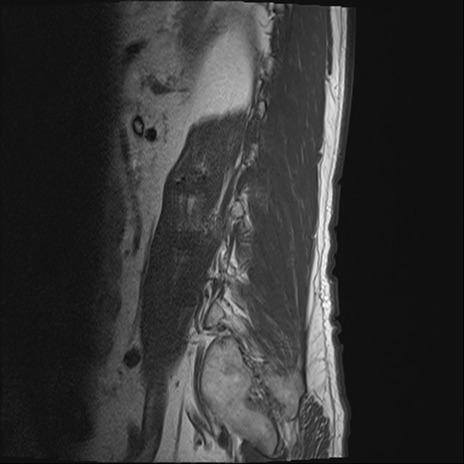

【症例】70歳代男性

【主訴】左下肢痛

【現病歴】2週間前くらいから腰痛、左下肢痛あり。左臀部から大腿、下腿外側のしびれが常時ある。歩行とともに同部位の痛みあり。

【身体所見】Lasegue70-/60+、Bragard-/±、PTR ±/±、ATR -/-、IP 5/5、TA 5/4、TS 5/5、EHL 右第1足趾なし/3、FHL 5/5、hypersthesia(-)、足背動脈触知良好

異常所見と診断は?